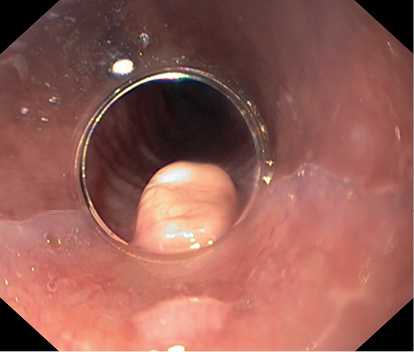

По данным ЭГДС, выполненной при поступлении: на фоне недостаточности кардии и неэрозивного рефлюкс-эзофагита на уровне 33 см от резцов по заднеправой стенке пищевода расположено экзофитное новообразование полиповидной формы размером 8×5 мм белесой окраски, выступающее в просвет на 4—5 мм, симптом шатра отрицательный (рис. 1, 2). Поверхность новообразования гладкая, сосудистый рисунок прослеживается.

Рис. 2. Новообразование по заднеправой стенке пищевода. Фото авторов.

В условиях хирургической операционной под эндотрахеальным наркозом в положении пациента на спине выполнено эндоскопическое удаление образования. Видеогастроскоп Olympus GIF-Н180J (Olympus, Япония) с фиксированным на дистальном конце прозрачным пластиковым колпачком проведен в просвет пищевода. По заднеправой стенке пищевода визуализировалось ранее выявленное экзофитное новообразование.